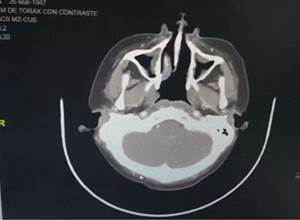

Among the auxiliary examinations of highlighted images presented, thickening of the mucosa in ethmoid cells, a radiolucent image in the upper palate (Figura 2), slight adenopathy at the retromandibular level (Figura 3), thickening of the mucosa of both maxillary sinuses, and thickening of the middle turbinate, there is a slight deviation to the left of the nasal septum (Figura 4), in the axial tomography of the head-lower part, a radiopaque image is appreciated in the left area of the palate, consistent with the necrosis evidenced in the physical examination , there is evidence of the presence of contrast hyper-uptake nodules and the presence of small adenopathies (Figura 5).

Figure 4. Head-upper axial tomography, evidence of thickening of the mucous membranes of both maxillary sinuses and thickening of the middle turbinate, there is a slight deviation to the left of the nasal septum, the slight circular radiopaque image on the anterior face of the right cerebellar peduncle ; no lymphadenopathy is seen.